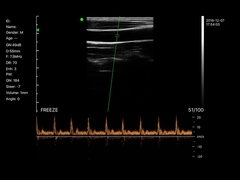

Calidad Escáner de ultrasonido portátil, analizador del ultrasonido del PDA Fabricante de China

Ultrasound scanner